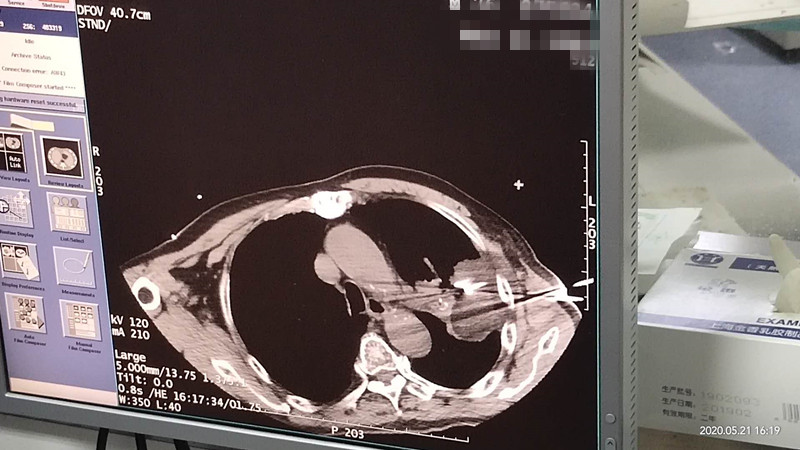

76岁肺部氩氦刀冷冻消融